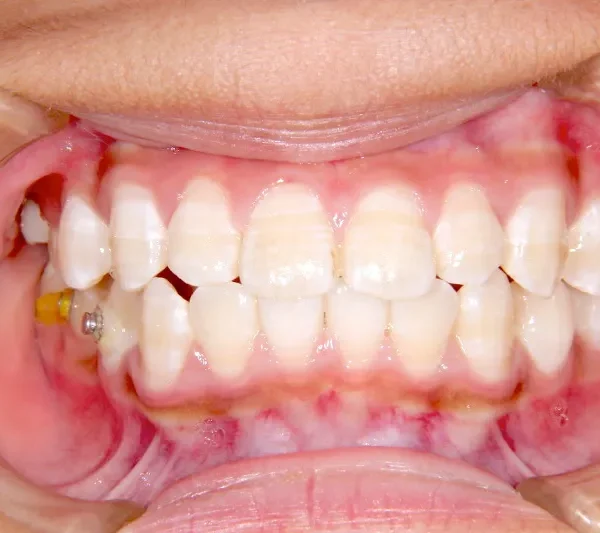

• 治療終了後

治療終了後

治療回数31回、4年11ヶ月の治療期間で矯正治療を終了しました。

主訴が改善され、ご満足頂きました。